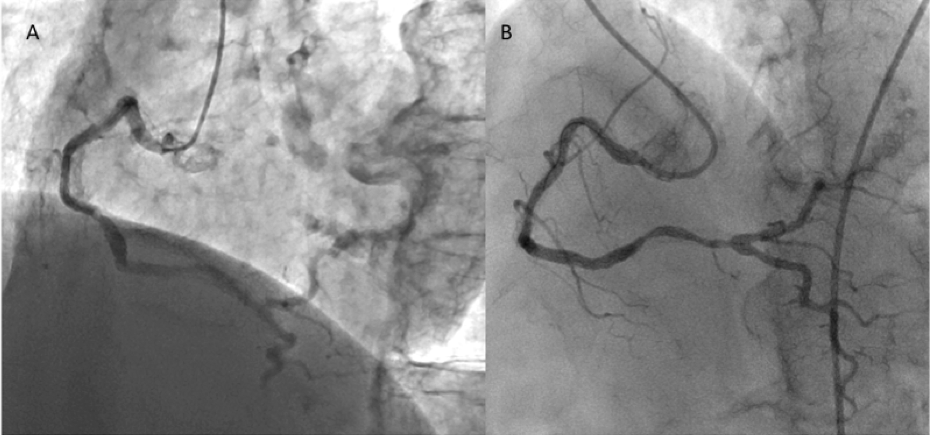

Figure 6. (A) Focal in-stent restenosis of the Nobori stent site and (B) angiogram after deployment of a 3.0 × 12 mm PROMUS Element stent (click thumbnail to view larger image).

Nine months after the Nobori stent implantation, the patient was admitted for chest pain on effort. Right coronary angiography revealed a focal significant ISR of the Nobori stent (Figure 6A), and plain fluoroscopic images showed a gap in the strut in the middle of the Nobori stent, suggesting SF (Figure 7B). The fractured segment was treated with a 3.0 × 12 mm PROMUS Element stent (Boston Scientific). No further imaging was possible because of severe calcification and tortuosity. Post-stenting angiography revealed an excellent result (Figure 6B).

Figure 7. Comparison of plain fluoroscopic images (A) immediately after Nobori stent deployment and (B) at the 9-month follow-up exam, showing a gap in the stent strut (arrowhead) (click thumbnail to view larger image).